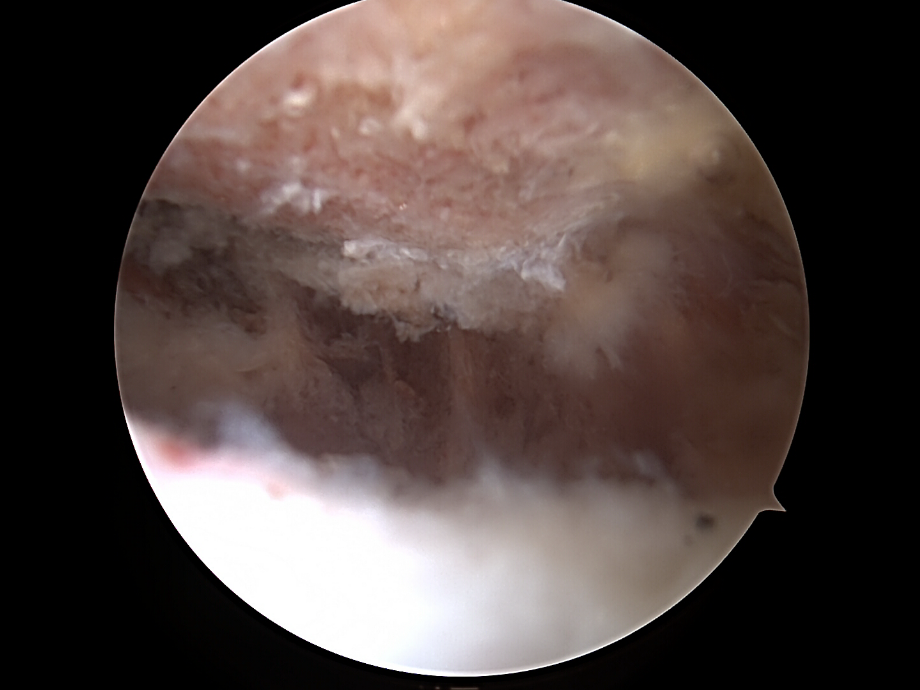

• Die Kamera wird in den subacromialen Raum vorgeschoben.

• Der oft entzündete Schleimbeutel (Bursa subacromialis) wird entfernt (Bursektomie), um Platz zu schaffen und die Sicht zu verbessern.

Dekompression

• Mit einer Fräse oder einem Shaver wird das  Akromion Schulterdach von innen geglättet (Akromioplastik).